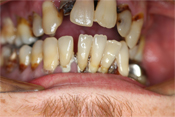

WORST TEETH Pictures from Warren Dentistry

This can happen to your teeth when proper Dental Hygiene is not practiced.

Patient 2